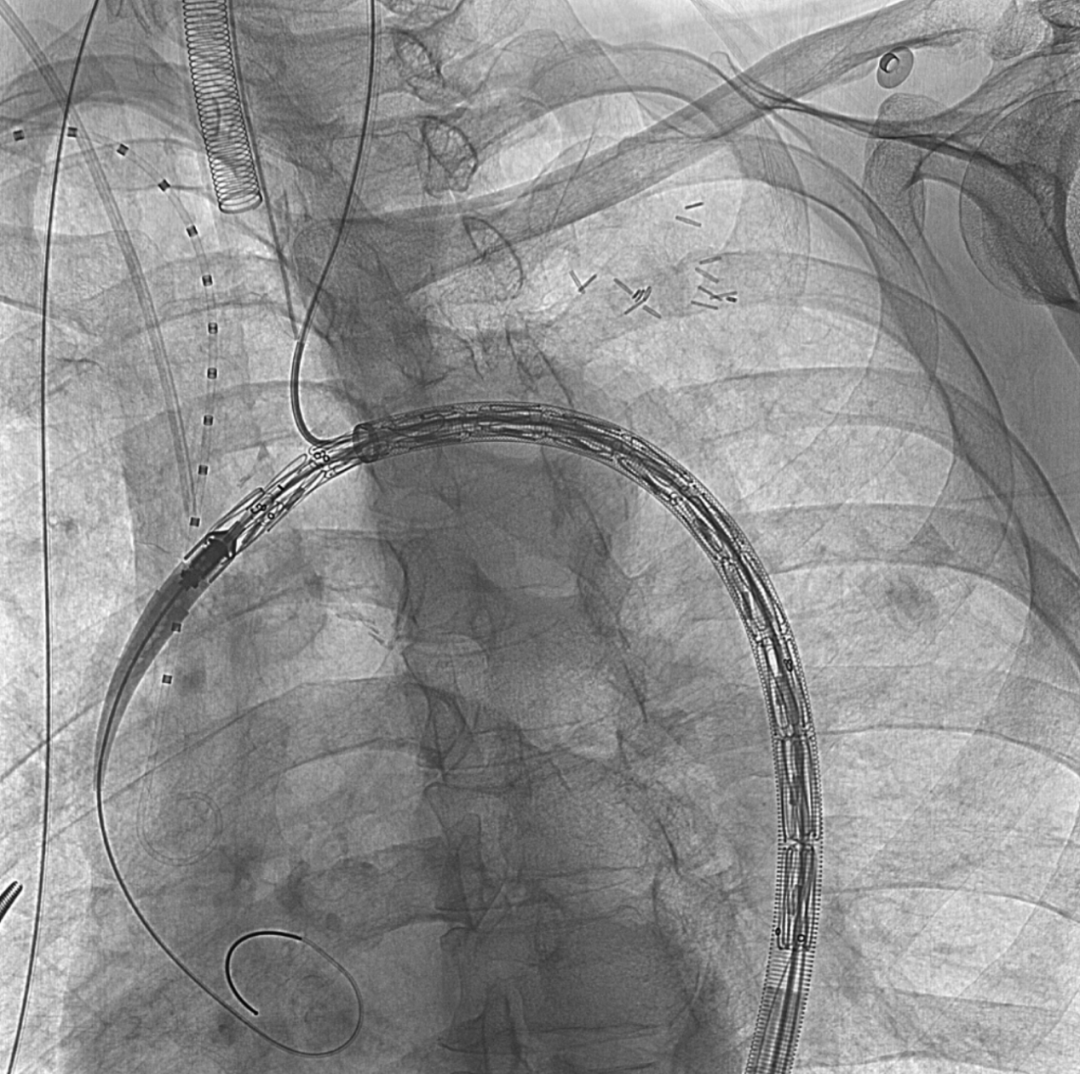

建立通路,输送主体覆膜支架至弓部,内嵌开口对位LCCA

图片

释放主体支架并用分支支架重建LCCA后造影,贴壁良好,但由于瘤体过大且偏前侧,有少量I型漏出现